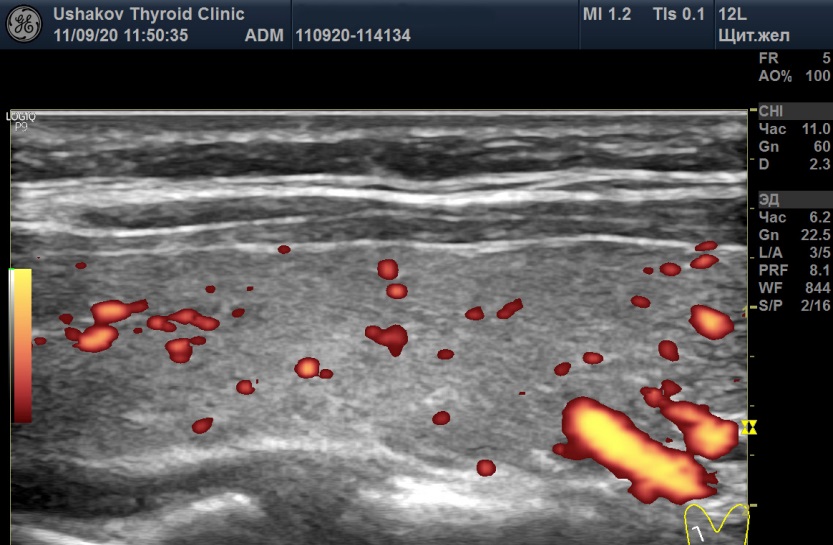

Рисунок 6 Правая доля щитовидной железы (в режиме энергетического допплера) пациентки С., 22 года. А – 04.08.20 в состоянии гипотиреоза и Б – 11.09.20 в состоянии гипертиреоза. Кровоток в каждой доле в разные даты в малой степени усилен, но значимых изменений интенсивности кровотока при этих УЗИ не выявлено.

Рисунок 7 Максимальная пиковая скорость крови в верхних правой и левой артериях щитовидной железы пациентки С., 22 года. А – 04.08.20 в правой артерии ПССК 59,9 см/с, Б – 11.09.20 в правой артерии ПССК 105 см/с.